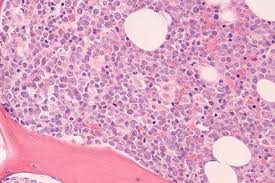

What Is Cancer Of Bone Marrow - Bone Marrow Cancer Treatment In India Bone Marrow Treatment Cost Medsurgeindia : Eventually you might not have enough healthy bone marrow to make blood cells.. That will offer him some concept what the issue is. If your doctor needs more info, he'll. In the diagnosis of bone marrow cancer, radiographic methods, bone scintigraphy, computed tomography (ct), and magnetic resonance imaging (mri) are required. How long will the procedure take? White blood cells fight off infections that enter the body.

Bone Marrow And Cancer Cells Survive In Ex Vivo Co Cultures A Download Scientific Diagram from www.researchgate.net Bone marrow cancer is a very broad term, there are many types of bone marrow cancer and according to that their signs and symptoms also change. What are the risks and benefits of having the procedure? Located deep within the marrow are stem cells, which can develop into red bone marrow cancer happens when cells in the marrow begin to grow abnormally or at an accelerated rate. How long will the procedure take? Bone cancer is rare, making up less than 1 percent of all cancers. Remember that blood cells include. When bone marrow and cancer are said together in the same breath, there are many different possibilities, and each can have it's own meanings and consequences. Myelodysplastic syndrome (mds) refers to a group of disorders in which the bone marrow.

Bone marrow cancer is a very broad term, there are many types of bone marrow cancer and according to that their signs and symptoms also change. Read about what happens when you have this test. This is what bone marrow cancer is all. Bone cancer is rare, making up less than 1 percent of all cancers. Learn more about these partnerships and how you too can join us in our. Remember that blood cells include. It'll likewise let him understand if you have a fever or infection. This tissue is made up of immature cells, which are known as stem cells, which develop into various types of blood cells such as: How long will the procedure take? Do you know what bone marrow cancer symptoms look like? In fact, noncancerous bone tumors are much more common than cancerous ones. The american cancer society's estimates for cancer of the bones and other kinds of cancers that are sometimes called bone cancers start in the blood forming cells of the bone marrow − not in the bone itself. These tumors are not considered primary bone cancers because they do not arise from the actual.

In this article, we discuss the different types of bone marrow cancer, including their symptoms and how to treat them. Located deep within the marrow are stem cells, which can develop into red bone marrow cancer happens when cells in the marrow begin to grow abnormally or at an accelerated rate. This is what bone marrow cancer is all. It may lead to greater than usual production of stem cells which then matures into any of the kinds of as the number of particular blood cells increases, cancer gets worse and results in the formation of tumours. As with any form of cancer, the key is being able to identify the signs and symptoms of the illness and take action before it becomes too serious.

Bone marrow contains a large number of stem cells. In adults, the bone marrow that makes the most blood cells is found in the hip bones (bones of the pelvis ), shoulder bones (scapula), bones of the spine (vertebrae), ribs, breast bone (sternum) and skull. Bone marrow cancer includes leukemias and multiple myeloma. A patient is diagnosed with bone marrow cancer and a hematocrit of 70 percent what is this condition called? What are the symptoms of bone marrow. Myeloproliferative disorders begin in the bone marrow and may cause a greater than normal number of stem cells to develop into one or more types of blood cells. Cancer cells can affect the bone marrow. Read about what happens when you have this test. Bone marrow cancer begins in the stem cells. These tumors are not considered primary bone cancers because they do not arise from the actual. Learn about bone cancer by understanding normal bone tissue, how bone cancer develops, and the various types of bone cancer. What is bone marrow suppression in children? First, recall that your bone marrow is like a factory, producing new blood cells all the time.